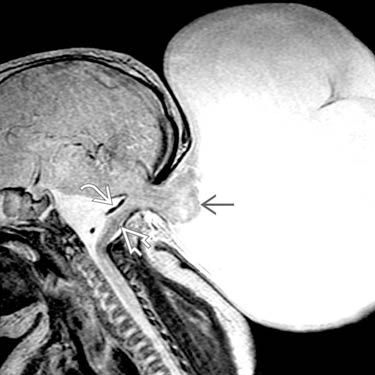

Dị dạng Chiari 2 thai nhi (Chiari 2 malformation)